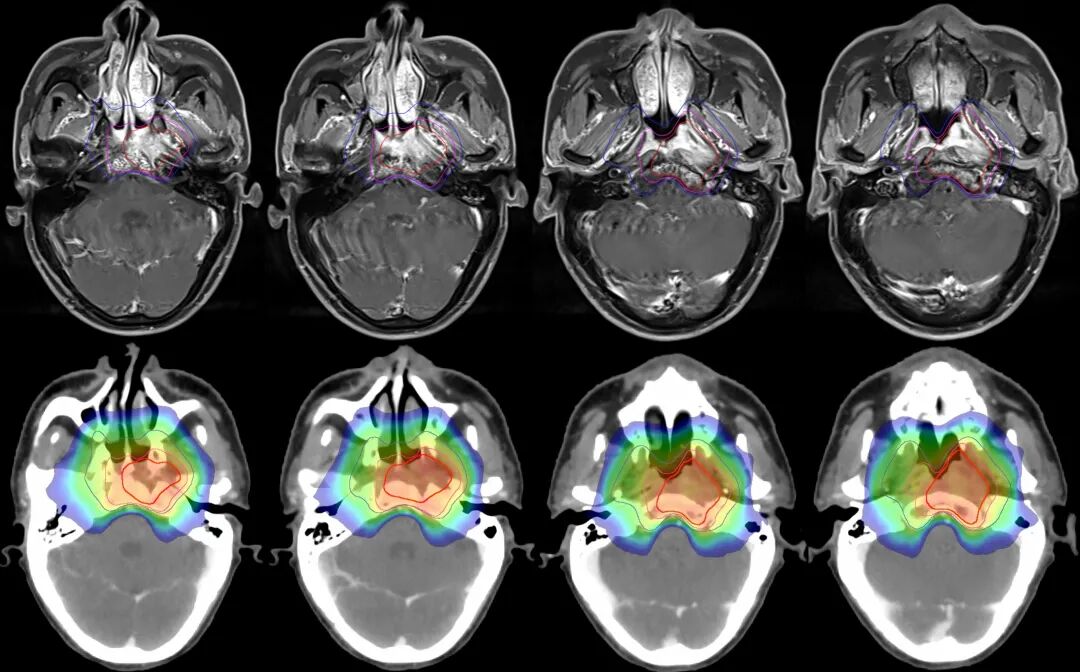

注解:360°容積弧形調(diào)強(qiáng)放療,高劑量集中在腫瘤區(qū)域,同時(shí)降低皮膚劑量。

圖注:上排紅線內(nèi)為腫瘤照射靶區(qū)。下排為劑量分布圖,可見中心區(qū)高劑量照射,周邊劑量快速跌落,形成銳利的集束聚焦照射,周圍重要器官得到良好保護(hù)。